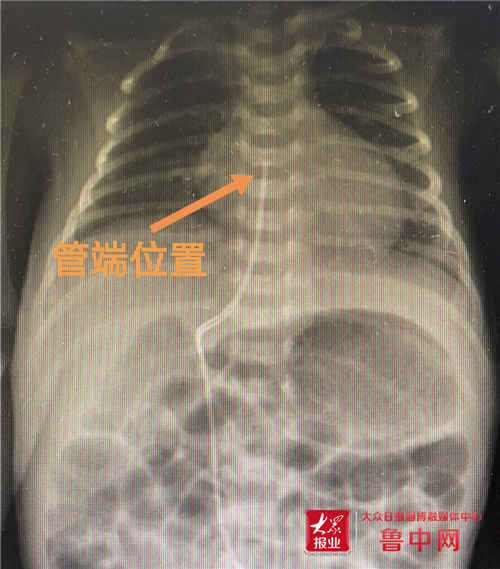

据了解,该婴儿胎龄31周,出生体重仅1.5kg,估计静脉营养时间长,外周静脉通路难以长时间保留,且反复穿刺难度较大,在输注高渗液体时,容易外渗造成皮下坏死。经山大二院李雅琼主任、新生儿科谢娜主任分析讨论,决定为该患儿行脐静脉置管术。操作过程顺利,置管后行胸部正位片确定导管位置。

脐静脉置管是将导管通过脐静脉植入下腔静脉,此处血流速度较快,输注高浓度、高渗透药物时可迅速被血流带走,在血管局部停留时间短,并且能迅速降低液体渗透压,可减少对血管壁的刺激,保证血管的完整性,这样静脉炎的发生率就会降低。并且,脐静脉置管易固定不易脱落、可保留2周时间,极大减少了穿刺困难及反复静脉穿刺给患儿带来的痛苦,尤其在早产儿、低出生体重儿生后早期阶段(2周内)应用,存在明显的优势,且不需要局部麻醉,节省时间和人力,同时缩短住院时间,降低住院费用。